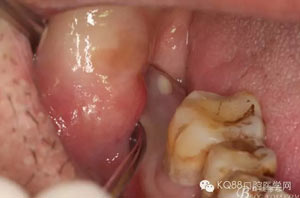

患者、孫xx、男,61歲。主訴:右側(cè)下頜后牙牙齦反復(fù)腫痛兩年。專科檢查:47缺失,牙槽嵴頂粘膜輕度紅腫,捫診有一瘺口溢膿,疼痛不明顯,開口度正常。CBCT影像檢查:48埋伏阻生,牙冠倒置,冠周有牙囊影像。牙冠近中與下頜管緊鄰,未有骨壁保護(hù)。診斷:埋伏倒置阻生伴發(fā)冠周炎。治療計(jì)劃:建議拔除48。術(shù)前和充分溝通,并告知術(shù)中和術(shù)后的可能出現(xiàn)的并發(fā)癥,患者簽知情同意書。

圖2.術(shù)前的CBC影像T檢查:48低位導(dǎo)致,近中牙尖緊鄰下頜神經(jīng)管。

圖3.其他方向的影像檢查:48近中牙冠與下頜管之間無骨壁相隔。